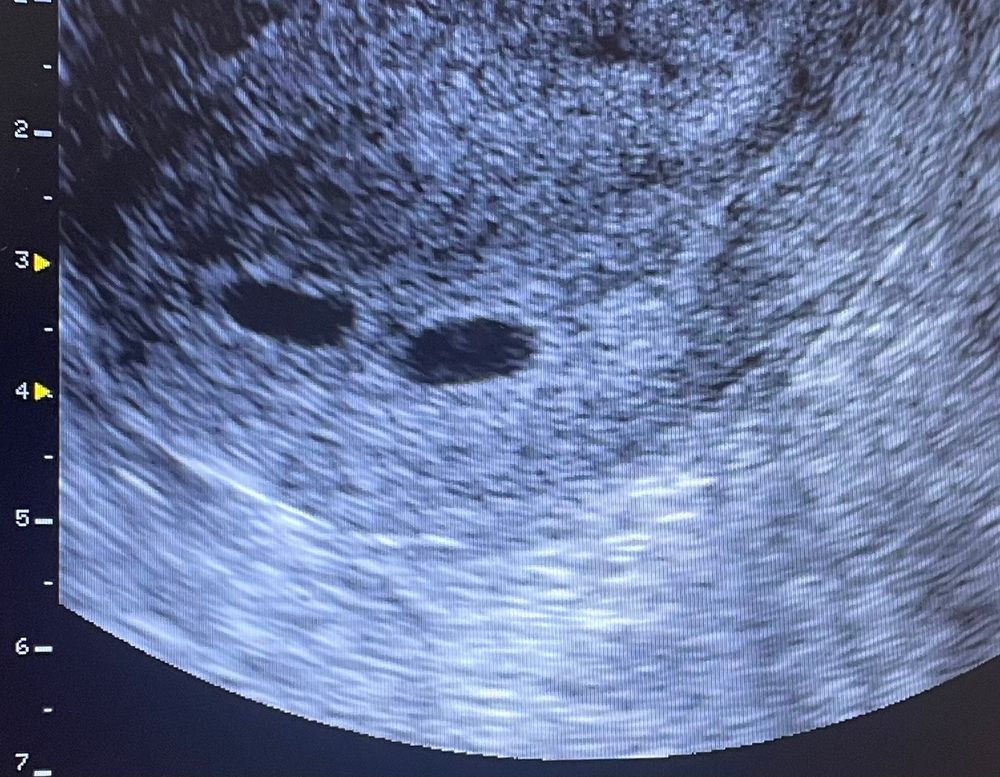

Ух ты, поздравляю!!!! В правом ПЯ я уже вижу ЖМ)